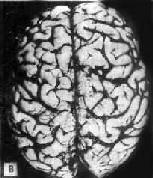

图16-32 初老期痴呆的脑 示脑明显萎缩(A),与正常脑(B)的对比 镜下,本病最主要的组织病变有:老年斑,神经原纤维缠结,颗粒空泡变性,Hirano小体等。 (1)老年斑:为细胞外结构,直径为20~150μm,最多见于内嗅区皮质、海马CA-1区,其次为额叶和顶叶皮质。银染色显示,斑块中心为一均匀的嗜银团,刚果红染色呈阳性反应,提示其中含淀粉样蛋白,其中含该蛋白的前体β/A-4蛋白及免疫球蛋白成分。中心周围有空晕环绕,外围有不规则嗜银颗粒或丝状物质。电镜下可见该斑块主要由多个异常扩张变性之轴索突触终末构成(图16-33)。